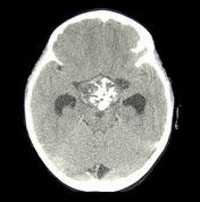

Диагностика заболевания достаточно сложна. Данных анамнеза, жалоб и симптоматики недостаточно для постановки диагноза. Дополнительно пациенту назначают клинический и биохимический анализы крови, анализ на содержание паратгормона, кальция, фосфатов в сыворотке крови, анализ на онкомаркеры, а также исследования для исключения поражения сердца, легких, почек. Визуализировать очаг помогают УЗИ, КТ, МРТ.

При спорных диагностических ситуациях, а также при подозрении на метастазы, проводятся позитронно-эмиссионная томография (ПЭТ), субтракционная сцинтиграфия.